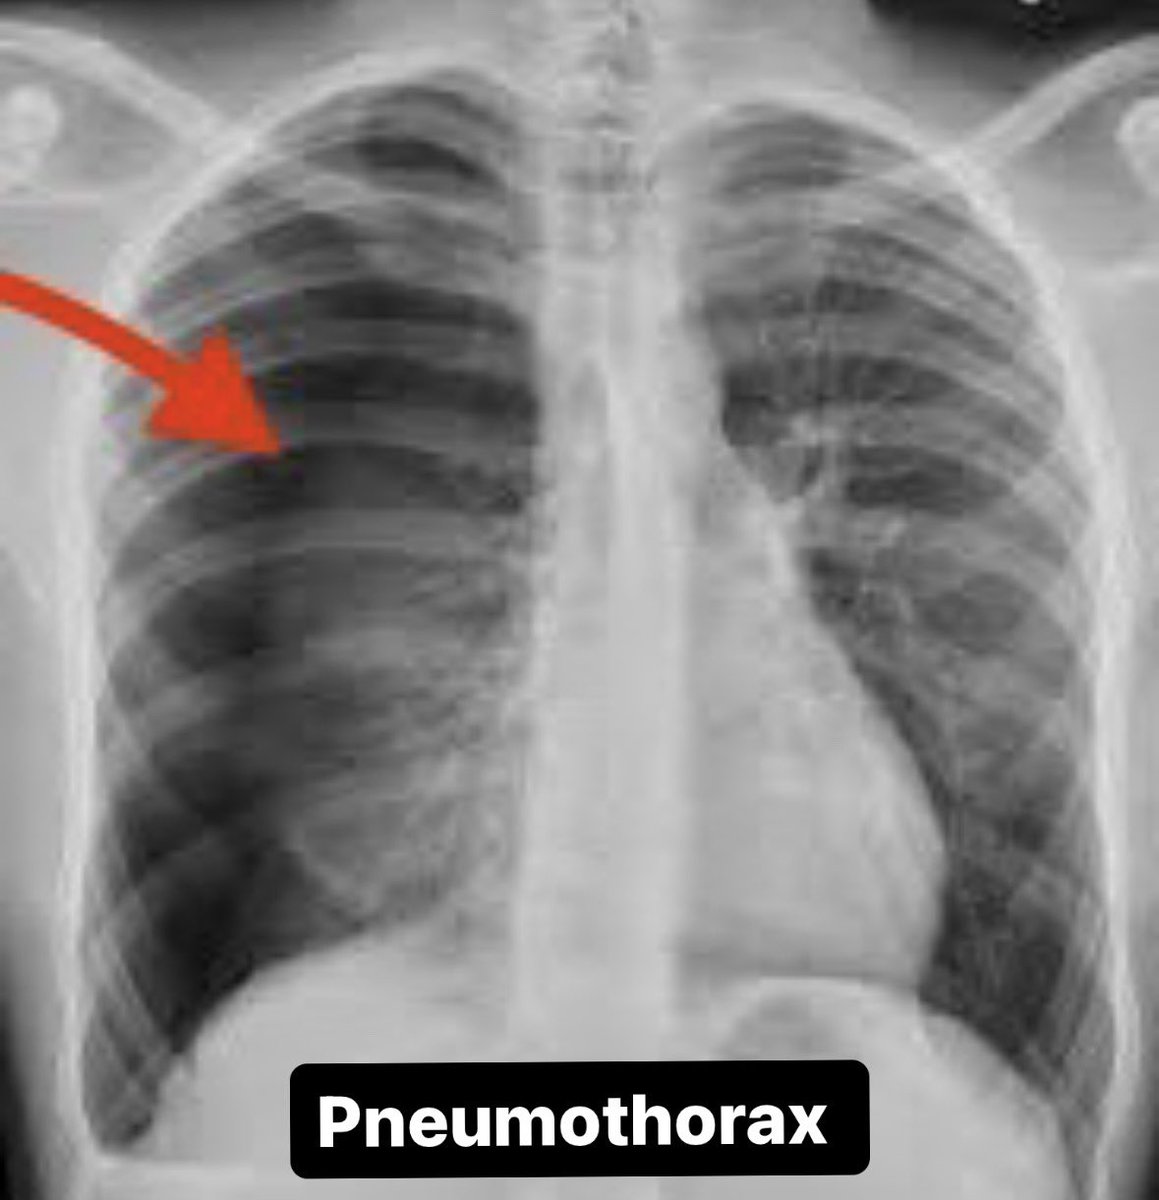

🚨 Thread: Radiology in Common Emergencies 🚨1/x #Medtwitter #radiology #Emergency potential #neetpg questions